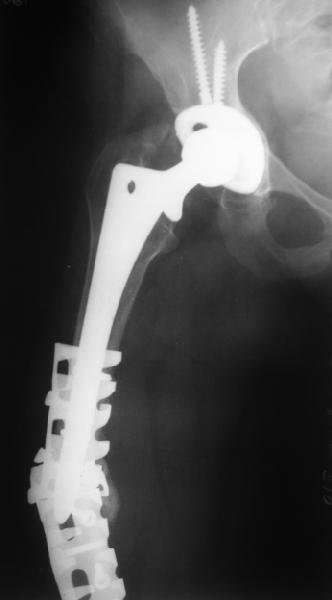

Female, rheumatoid, THA in 2003, car accident in 2006, failed plating. Nailing in Oct 2007. The nail is solid with hollow proximal part where the stem is docked. Last images are in 1 year after

nailing.

Спасибо за обсуждение. После нескольких дней тракции аппаратом сделали. Попытка закрытой репозиции не удалась из-за смещения по ширине, мешали фрагменты цемента. После их удаления репозиция получилась. Еще убрали немного цемента с ножки по латерльной стороне, чтобы обнажить 40-50 мм ее дистальной части, для плотной посадки гвоздя. Дальнейшее введение гвоздя было несложным. Протез показался нам стабильным в проксимальной части как латерально, так и медиально. Картинки в приложении.

THX for the discussion. After few days of traction by ex-fix the surgery was performed. An attempt of closed nailing was unsuccesful because of fragment translation, which was blocked by cement fragments. After removal of broken cement pieces reduction was reached "automagically". Also some cement from lateral part was removed by

chisel to expose distal 40-50 mm of the stem to allow tight fit of the nail. Further fixation by the nail was pretty easy and straightforward. Images attached. The stem looked stable in its proximal part both laterally and medially. Comments/critics are welcome.